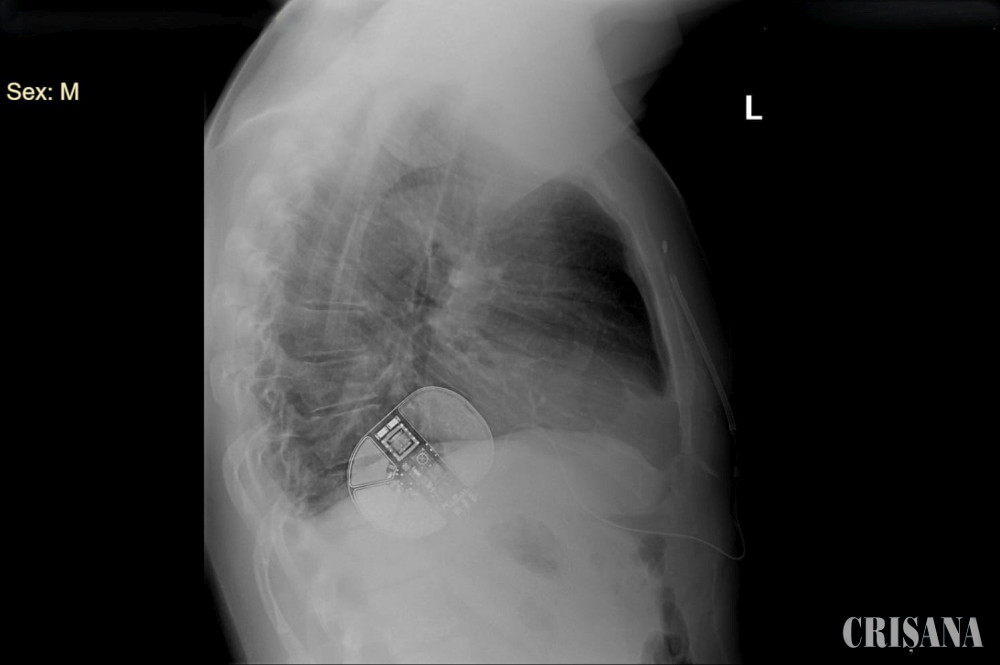

Astfel, pe 6 septembrie, a avut loc în premieră județeană intervenția de implantare a defibrilatorului cardiac subcutanat. Aceasta s-a desfășurat în sala de electrofiziologie, sub control fluoroscopic, ceea ce presupune efectuarea unei proceduri imagistice prin care se obțin imagini în timp real cu ajutorul razelor X.

Pacientului i s-a efectuat anestezie generală și loco-regională intercostală. Procedura a decurs asemănător cu procedura de implantare a unui stimulator cardiac permanent, însă a necesitat o etapă suplimentară legată de testarea și programarea defibrilatorului. S-au efectuat două incizii: una la nivelul latero-toracic stang și o incizie mică la nivel toracic anterior. Medicul intervenționist a creat un buzunar subcutan (sub piele) latero-toracic, pentru implantarea dispozitivului, după care au fost plasate cele două sonde de defibrilare la nivel pre-sternal și latero-toracic stâng. S-a indus aritmia, în scopul de a cauza un stop-cardio respirator pentru testarea funcționalității aparatului. Terapia a fost un succes și s-a confirmat funcționalitatea defibrilatorului. Intervenția a decurs bine și a durat 3 ore.